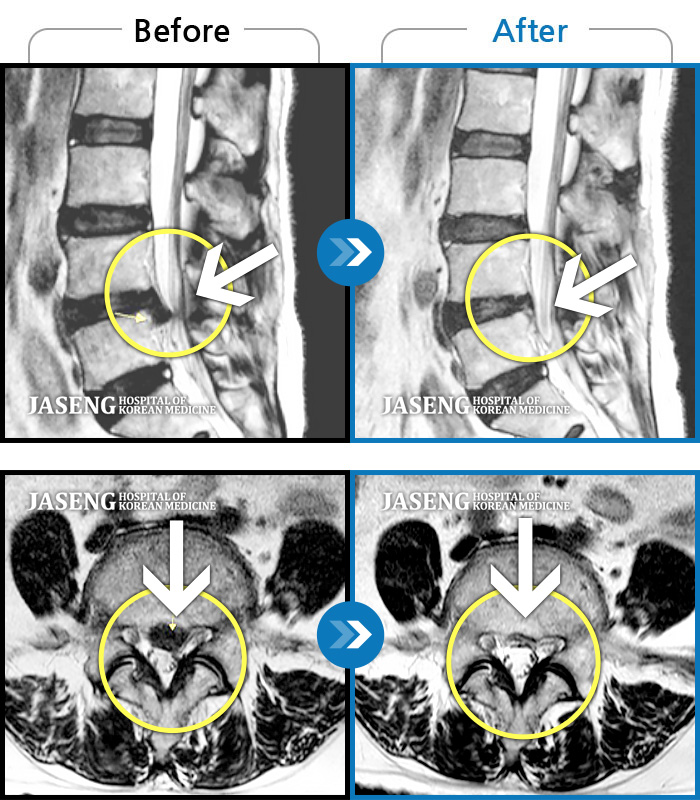

Before

After

허리통증, 왼쪽 다리 저림 및 통증

2018.06.18 ~ 2019.05.16